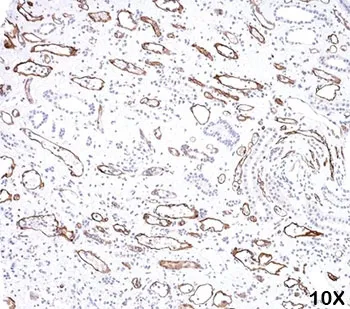

C4d / Complement 4d Antibody

This antibody is specific to Complement 4d (C4d) and it reacts with the secreted as well as cell-bound protein. C4d is a degradation product of the activated complement factor C4b. Complement 4b is typically activated by binding of antibodies to specific target molecules. Following activation and degradation of the C4 molecule, thio-ester groups are exposed, which allow transient, covalent binding of the degradation product C4d to endothelial cell surfaces and extracellular matrix components of vascular basement membranes near the sites of C4 activation. The presence of C4d in peritubular capillaries is a key indicator for acute humoral (i.e. antibody-mediated) rejection of kidney, heart, pancreas and lung allografts. As an established marker of antibody-mediated acute renal allograft rejection and its proclivity for endothelium, this component can be detected in peritubular capillaries in chronic renal allograft rejection as well as hyperacute rejection, acute vascular rejection, acute cellular rejection, and borderline rejection. C4d has been shown to be a significant predictor of transplant kidney graft survival. C4d antibody, combined with antibody to C3d, can be utilized as a tool for diagnosis of allograft rejection that may warrant a prompt and aggressive anti-rejection treatment.Host:

ELISA, IHC-PFormat: